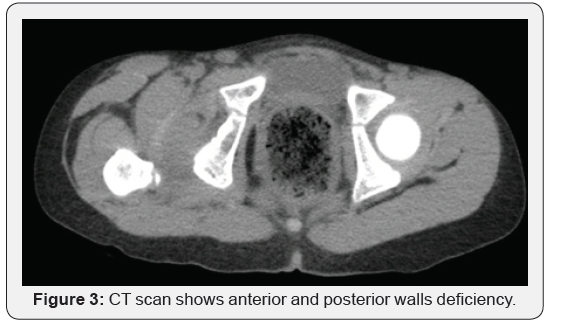

Physical examination revealed prominent limping on ambulation, positive Galeazzi sign (Figure 1), femoral head could be palpated in the right groin region, and the girl was pain free throughout her right hip range of motions. She had generalized join laxity and muscle hypotonia. Radiological examination confirmed right hip dislocation. CT scan demonstrated anterior position of femoral head, shallow acetabulum with severe anterior and posterior wall deficiency (Figures 2 & 3), and signs of soft tissue interposition. Acetabulum index was measured as 33 degree (Figure 4) and femoral anteversion as 70 degree.